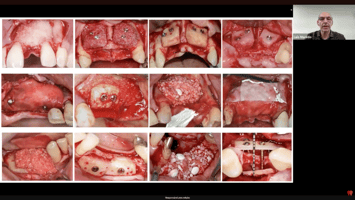

Na aula os professores apresentaram casos reais que ilustraram perfeitamente esse ponto. Um dos exemplos mais marcantes é o de um paciente jovem que recebeu um implante de incisivo lateral totalmente vestibularizado, exigindo sua remoção e refazimento. Em outro caso, um implante imediato foi colocado excessivamente coronal, o que o especialista chamou de “morte programada”.

Esses erros não ocorreram por falta de técnica, mas por falhas de planejamento e deixam evidente por que o ambiente virtual é hoje indispensável. O planejamento digital reduz variações, antecipa problemas, corrige angulações impossíveis de prever clinicamente e estabelece limites biológicos e mecânicos antes mesmo de a broca tocar o osso.

Casos Avançados: A Prática Comprovando a Teoria

Os casos clínicos apresentados demonstram com clareza a capacidade das tecnologias digitais de transformar cirurgias complexas em procedimentos mais previsíveis.

Foi demonstrado, por exemplo:

• Recobrimento radicular associado a implante imediato, com uso simultâneo da guia para permitir uma execução flapless e, ao mesmo tempo, viabilizar um retalho avançado de Zucchelli.

• Correção de extremo livre com guia mucosuportada, usando pinos de fixação para garantir estabilidade.

• Implante imediato com carga realizada a partir de extração flapless guiada, permitindo controle do envelope ósseo.

Esses exemplos reforçam que a tecnologia não elimina a necessidade de habilidade, mas expande as possibilidades do cirurgião experiente.